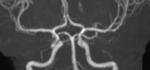

Here are two examples of artificial intelligence (AI) driven pulmonary embolism (PE) response team apps featured by vendors Aidoc and Viz.AI at the 2021 Radiological Society of North America (RSNA) 2021 meeting.

The AI scans computed tomography (CT) image datasets as they came off the imaging system and looked for evidence of PE. If detected by the algorithm, it immediately sends an alert to the stroke care team members via smartphone messaging. This is done before the images are even loaded into the PACS. The radiologist on the team can use a link on the app to open the CT dataset and has basic tools for scrolling, windowing and leveling to determine if there is a PE and the severity. The team can then use the app to send messages, access patient information, imaging and reports. This enabled them all to be on the same page and can communicate quickly via mobile devices, rather than being required to use dedicated workstations in the hospital.

Both vendors showed similar apps for stroke at RSNA 2019. That idea for rapid alerts, diagnosis and communications for acute care teams has now expanded to PE and also for aortic dissection and abdominal aortic aneurysms (AAA). AI.Viz and Aidoc are looking at expanding this type of technology for other acute care team rolls, including heart failure response.